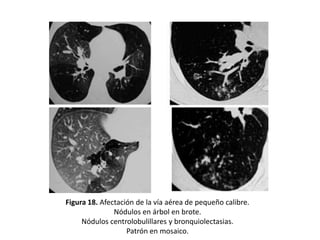

• Son también frecuentes los signos relacionados con la afectación de

la vía aérea de pequeño calibre (bronquiolos) como:

– Nódulos en árbol en brote

– Nódulos centrolobulillares

– Bronquiolectasias.

• Pueden traducir zonas de bronquiolitis, lo que puede considerarse

un hallazgo precoz (Figura 18).

Figura 18. Afectación de la vía aérea de pequeño calibre.

Nódulos en árbol en brote.

Nódulos centrolobulillares y bronquiolectasias.

Patrón en mosaico.